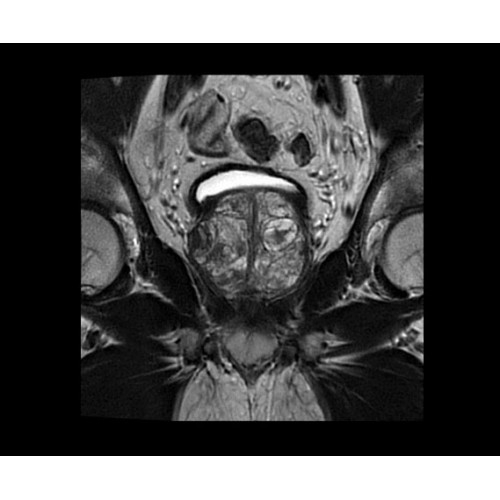

SIGNA PET/MR 3.0T — это гибридная система, в которой совмещаются две принципиально разные технологии — магнитно-резонансную томографию (МРТ) и позитронно-эмиссионную томографию (ПЭТ). Система отличающийся высокой чувствительностью и эффективностью и предназначена для диагностики в области онкологии, неврологии, кардио-васкулярных исследований, исследований воспалительных процессов.

Компания GE Healthcare представляет революционную, полностью интегрированную систему SIGNA PET/MR1, в которой сочетаются времяпролетная технология (TOF) и возможности напряженности магнитного поля 3.0 Тл. Мы поможем вам поднять исследования на более высокий уровень. SIGNA PET/MR позволяет достичь впечатляющей точности и скорости исследований, а благодаря новейшей технологии реконструкции Q.Clear2 качество изображений улучшается в два раза. Кроме того, в систему включен полный набор клинических приложений и гибких катушек для проведения любых видов исследования, открывая для вас возможности визуализации, о которых вы даже не догадывались.

Впечатляющие клинические возможности

Система SIGNA PET/MR предлагает впечатляющие клинические возможности и открывает доступ к наиболее полным пакетам программных приложений.

• TurboTOF — инновационная технология позволяет корректировать коэффициент затухания сигнала и минимизировать потери анатомических данных, создавая МР-систему для количественной визуализации.

• Q.Clear — в основу технологии легли накопленные знания о том, как минимизировать помехи при реконструкции и получить четкое изображение. При значительном улучшении качества изображения сохраняется точность расчетов. Сочетание технологии TOF и реконструкции Q.Clear — ваш надежный помощник для получения точных и достоверных данных.

• МРТ с функцией нулевого времени эхо (ZTE) отличается точностью, возможностью персональных настроек и отсутствием ионизирующего излучения. Она приходит на смену традиционному исследованию на основе рентгеновского излучения. МРТ с функцией нулевого времени эхо (ZTE) на базе SIGNA ПЭТ/МРТ является более надежной и быстрой по сравнению с системами, использующими сверхмалое время эхо (UTE).

• Приложения для коррекции артефактов движения — используйте наиболее широкий набор инструментов, таких как PROPELLER, PROMO и навигаторы Pencil Beam, позволяющих снизить влияние непроизвольных или физиологических движений на качество изображений.